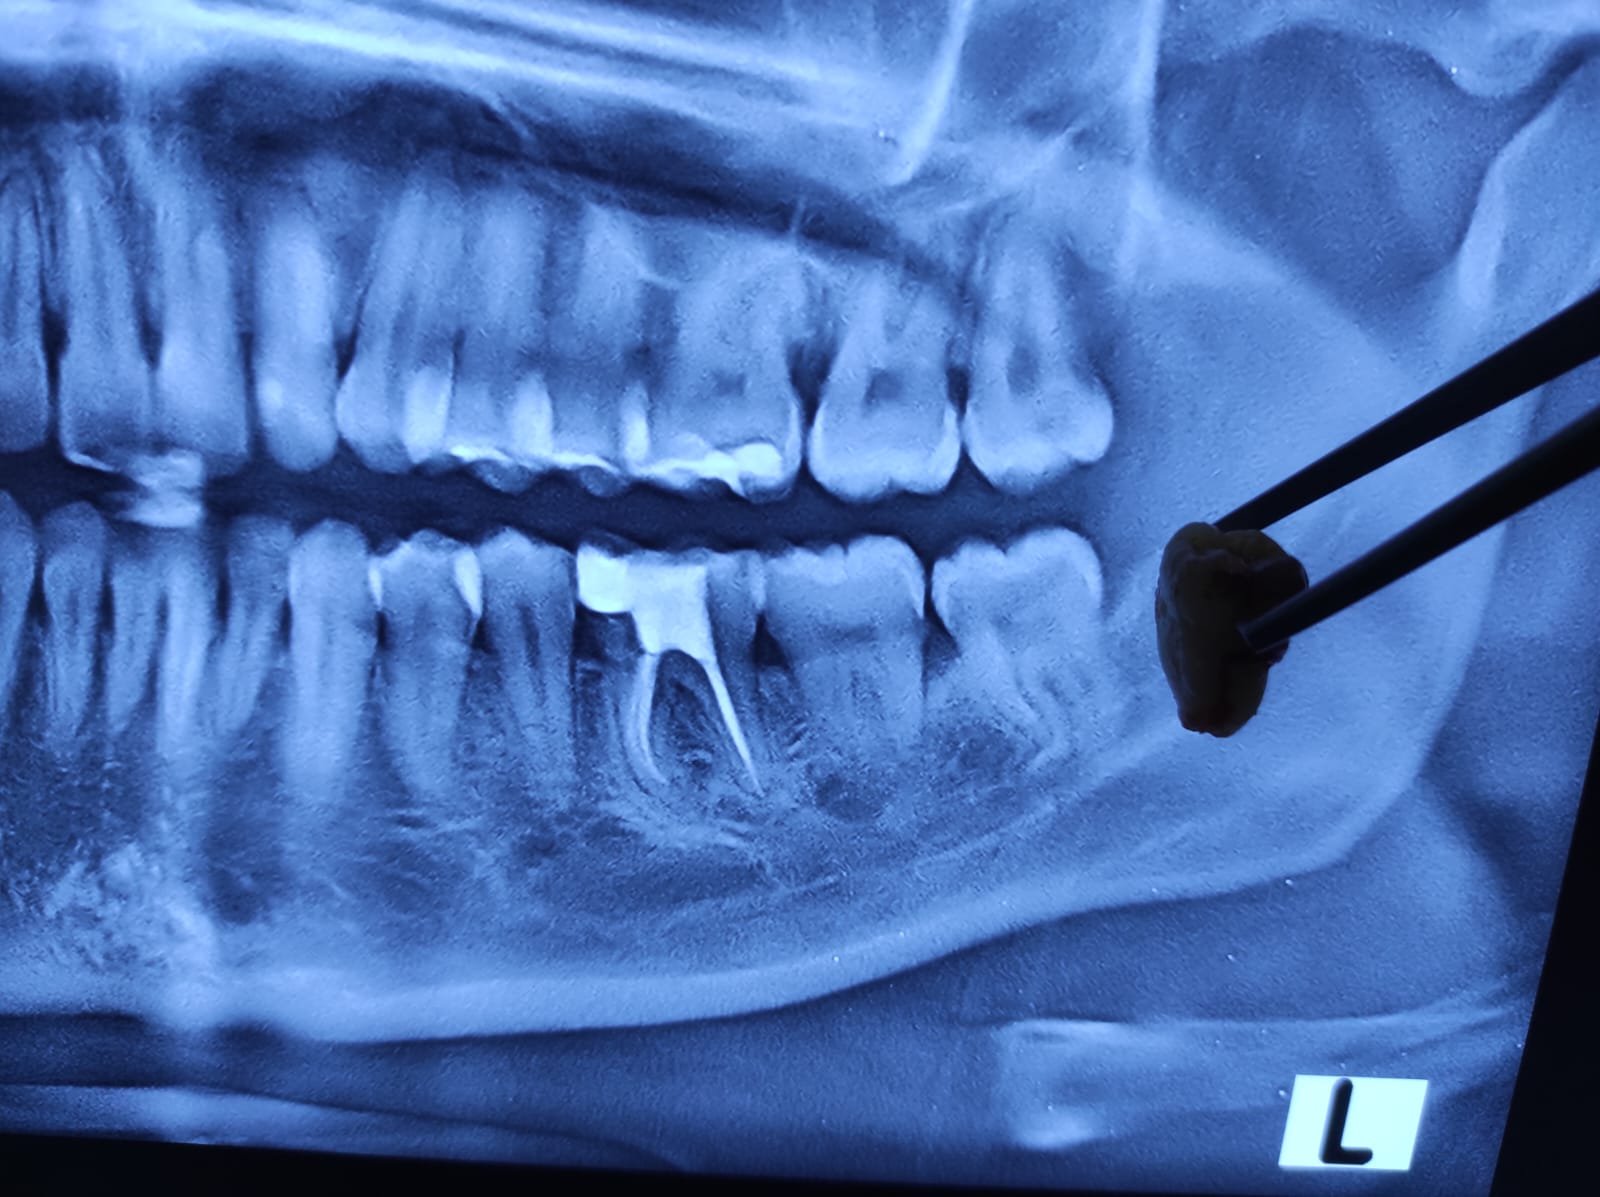

Prosedur odontektomi gigi bungsu di jakarta

Bagaimana Prosedur Odontektomi Dilakukan?

Dokter gigi bedah mulut melaksanakan odontektomi dengan beberapa langkah berikut:

1. Pemeriksaan awal

Dokter melakukan rontgen panoramic untuk melihat posisi gigi bungsu dan menilai kondisi pasien.